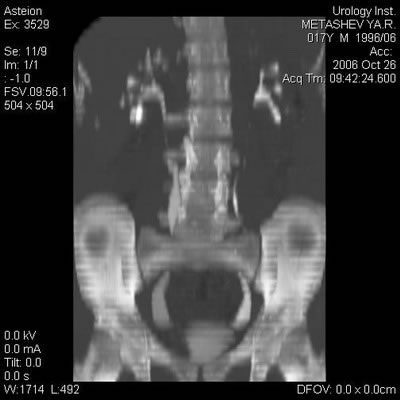

Компьютерная томография

Цистография

Динамическая нефросцинтиграфия – изображение

правой почки с неровными контурами и удовлетворительным

накоплением РФП в паренхиме. Изображение левой почки уменьшено

в размерах. Накопление РФП в паренхиме неравномерное, снижено.

Визуализируются оба расширенных мочеточника. Секреторная

функция правой почки снижена. Дефицит очищения 23%.

Эвакуация РФП замедлена на уровне ЧЛС. Секреторная функция

левой почки снижена. Дефицит очищения 31%.

Эвакуация РФП умеренно замедлена, неравномерная.